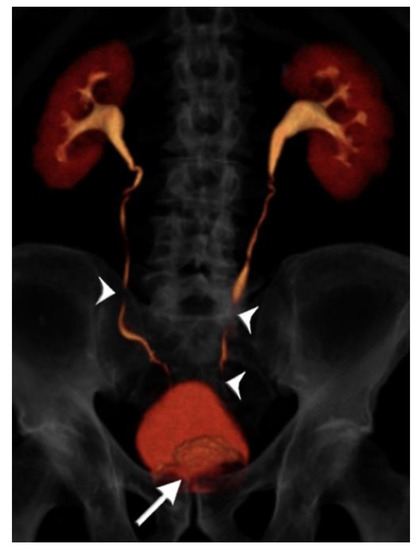

2.2. CT Urography Technique

- Cheng, K.; Cassidy, F.; Aganovic, L.; Taddonio, M.; Vahdat, N. CT urography: How to optimize the technique. Abdom. Radiol. 2019, 44, 3786–3799. [Google Scholar] [CrossRef]